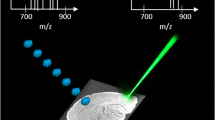

Matrix-assisted laser desorption/ionization time-of-flight mass spectrometry imaging (MALDI MSI)12,13 can be used to determine the spatial distribution of various compounds in tissue with a single label-free measurement. MALDI MSI has been used for a variety of applications, ranging from bioanalysis14,15 of lipids16,17, proteins, peptides, drugs and their metabolites18 to the detection of polymers in a biological environment19,20. Although several imaging applications for the visualization of abundant, endogenous phospholipid species exist16, MALDI MSI of phospholipids in phospholipid-based liposomal drug carriers in-vivo has not been reported yet. Analytical method development for applications of MALDI MSI in the drug delivery field are generally underexplored, as only a single study monitoring the non-natural cationic lipid DLin-KC2-DMA in lipid nanoparticle-formulated siRNA by MALDI MSI in mice has been published21.

Design of liposomal carriers and strategy for monitoring of liposomal integrity

Radiolabeled liposomal constituents enable evaluation of the in-vivo distribution of liposomal drug carriers with very high sensitivity. However, since only a single radiolabel can be monitored at any given time, radiochemical methods do not permit the evaluation of in-vivo liposome integrity or cargo retention and release. We hypothesized that MALDI MSI as a label-free method for simultaneous imaging of multiple masses may enable an innovative workflow that combines multiple MSI experiments across different mass scales in both polarities to address these questions in a single tissue slice. The main rationales for the present study was the following: If liposomal carriers contained two distinct markers that could be visualized by MSI, then non-co-localization would indicate disintegration, whereas co-localization would indicate liposome integrity. Similarly, co-localization of the liposome marker ion signals with the one for hemoglobin would indicate that the liposome was in a blood vessel. To this end, we chose two marker lipids that served as liposomal mass markers.

Endogenous phosphatidylglycerols display nearly no distinct background signals, as only small amounts are observed in tissue besides the lung22. Furthermore, phosphatidylglycerols are componens of known liposomal formulations. Therefore, we added DPPG (m/z 721.5) as a marker to the liposomal drug carriers besides egg phosphatidylcholine (EPC) and cholesterol. Since PEG-conjugated lipids are often used in drug formulations as a means for increasing plasma half-life of liposomes, we chose a synthetic polyethylenglycol- (PEG-) conjugated lipid as the second distinct mass marker for liposomes. However, PEGs are commonly synthesized by polymerization of ethylene oxide and are commercially available as mixed polymers that cover a wide range of molecular masses. Consequently, the often-used PEG2000-1,2-distearoyl-sn-glycero-3-phosphoethanolamine (DSPE) shows a broad molecular mass distribution that results in dilution of signal and decreased intensity (Fig. 1). Therefore, we incorporated the monodisperse N-(Carbonyl-methoxypolyethylenglycol-1618)-DSPE (PEG36-DSPE; m/z 2435.5 [M+Na]+, m/z 2451.5 [M+K]+, m/z 2467.5 [M-Na+2K]+), a defined 36-mer, into liposomes. Finally, we incorporated indocyanine green (ICG)23, the first fluorophore approved to test hepatic function in the 1970s24. It is a well-known drug surrogate that is established in many clinical applications and has been used in humans as well as animals for cancer detection using optical imaging25. In conclusion, our model liposomes were prepared with EPC, DPPG, cholesterol and PEG36-DSPE in a molar ratio of 27.5:27.5:40:5 and were loaded with 2 mM ICG. The particle size distribution had a Z-Average of 216.2 ± 0.8 nm, as assessed by dynamic light scattering.

Whereas for MALDI MSI of phospholipids in positive ion mode 2,5-dihydroxybenzoic acid (DHB) matrix is often preferred16, the suitable matrix for the detection of synthetic polymers depends on their chemical structure28. Often the best spectra are obtained if solubility of polymer and matrix match29,30. Therefore, polar matrices like DHB or 4-Hydroxy-α-cyanocinnamic acid (HCCA) may be suitable for hydrophilic polyethylene glycol species, but no report for MALDI MSI of PEG-lipid hybrids in tissue has been published. Although DHB has successfully been used for MALDI MSI of synthetic PEG31, the laser threshold for DHB is high for a 355 nm Smartbeam II laser. Excess energy may cause fragmentation of PEG36-DSPE (Suppl. Figure S02A). Therefore, we compared three different matrices: While DHB and HCCA resulted in higher intensities for the polymer-lipid-hybrid, PhCCAA showed the lowest background on MALDI steel targets (Suppl. Figure S02B). For comparison of matrices after administration of PEG36-DSPE containing liposomes to mice, reported sample preparation methods for detection of polymers with DHB and HCCA matrix20 were compared to the sample preparation method for lipid detection with PhCCAA matrix that we reported earlier26 (Suppl. Figure S02C). Although DHB was the best choice for detection of polysulfone and polyvinylpyrrolidone20, it was not possible to detect the PEG-lipid-hybrid after administration to mice with this sample preparation method. HCCA matrix led to strong fragmentation, whereas PhCCAA showed the lowest fragmentation of PEG36-DSPE on the tissue compared to the starting material. Take advantage of the opportunity to detect all liposomal components with the same sample preparation method, we chose PhCCAA for detection of DPPG and ICG in reflector negative mode and PEG36-DSPE in reflector positive mode.